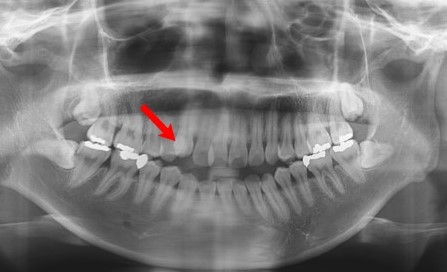

자 그럼 실제 엑스레이 사진을 보면서 설명드리도록 하겠습니다

빨간 화살표가 가리키고 있는 곳 보이시죠 엑스레이상으로도 보이지만

치아가 겹쳐 있는 것이 보입니다. 덧니인 것이죠